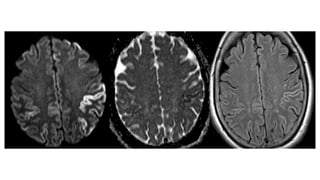

RADIOGRAPHIC FEATURES MRI MRI findingsmay be bilateral or unilateral and symmetric or asymmetric, and include: T2 hyperintensity obasal ganglia (putamen and caudate) othalamus ( hockey stick sign and pulvinar sign) ocortex: most common early manifestation owhite matter persistent restricted diffusion on DWI (considered the most sensitive sign) Review of sequential studies also typically demonstrates rapidly progressive cerebral atrophy.

• 52.